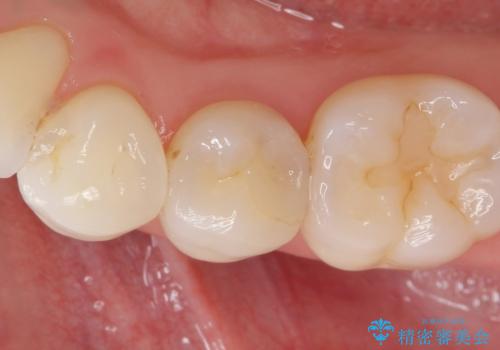

歯茎が腫れた。ジルコニアクラウンやりかえ。

歯茎が腫れたとの事で歯の神経が失活していたので精密根管治療を行い、ジルコニアクラウンで治療を行いました。

- ジルコニアクラウンスタンダード・仮歯 12.1万円 精密根管治療(イニシャルトリートメント)・ファイバーコア 13.2万円費用は治療当時の料金となります